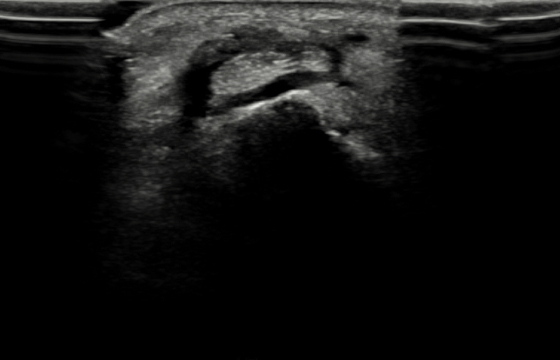

손목건초염 환자의 초음파 사진

2021.03.26

염증 조직으로 힘줄이 조여있는 모습 (검은색 부분)